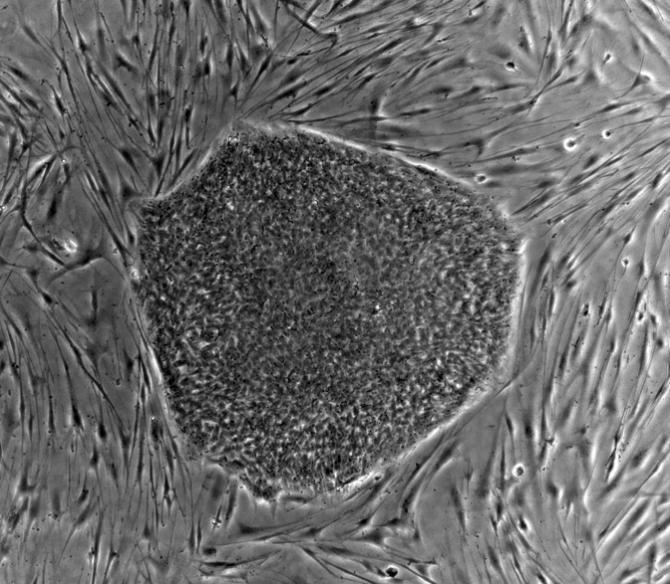

人類胚胎干細(xì)胞(hES)

人類與其他的脊椎動(dòng)物一樣,都是由200種以上細(xì)胞構(gòu)成的,特定的細(xì)胞類型具有特定的功能。例如:大腦中的神經(jīng)細(xì)胞負(fù)責(zé)傳遞信息,血紅細(xì)胞負(fù)責(zé)運(yùn)輸氧氣,皮膚細(xì)胞負(fù)責(zé)為機(jī)體提供保護(hù),以上的細(xì)胞都包含了獨(dú)一無(wú)二的DNA序列。雖然所有細(xì)胞的遺傳信息都是相同的,但各自的表達(dá)的模式有所不同,這便形成了具有不同功能的細(xì)胞。當(dāng)人出生之后,大多數(shù)細(xì)胞的表達(dá)模式就固定下來(lái)了,如果神經(jīng)細(xì)胞受到了損傷,紅細(xì)胞也當(dāng)然不會(huì)突然變?yōu)樯窠?jīng)細(xì)胞并對(duì)受損的組織進(jìn)行修補(bǔ)。